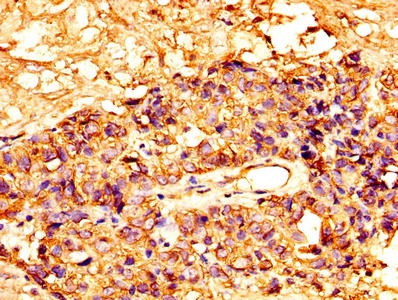

• IHC image of CSB-PA10159A0Rb diluted at 1:300 and staining in paraffin-embedded human breast cancer performed on a Leica BondTM system. After dewaxing and hydration, antigen retrieval was mediated by high pressure in a citrate buffer (pH 6.0). Section was blocked with 10% normal goat serum 30min at RT. Then primary antibody (1% BSA) was incubated at 4°C overnight. The primary is detected by a biotinylated secondary antibody and visualized using an HRP conjugated SP system.